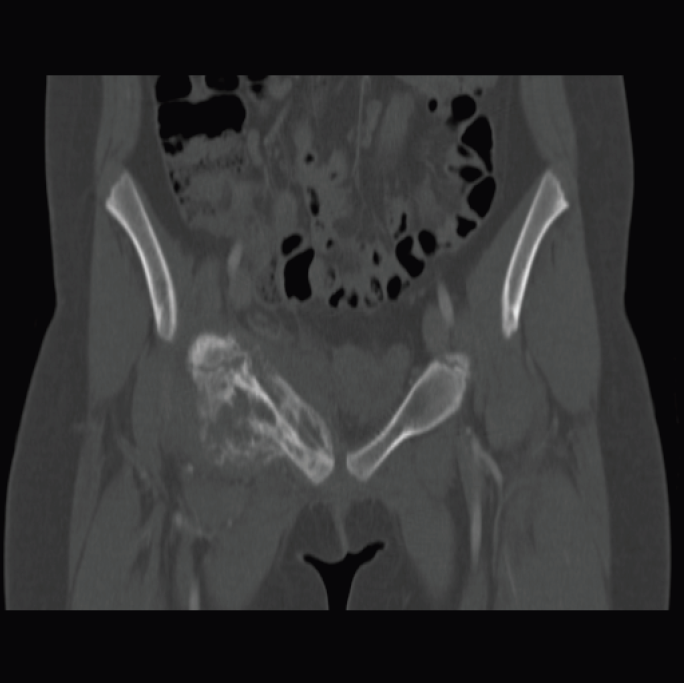

The radiograph of the girl’s pelvis (Figure 3) revealed onion-skin periostitis along the right superior pubic ramus. Computed tomography (CT) scanning of the pelvis was performed for further evaluation of the radiography findings. The CT images (Figures 4, 5 and 6) showed a permeative lesion that involved the entire right superior pubic ramus, with cortical destruction and onion-skin periostitis that were concerning for malignancy. The diagnosis of Ewing sarcoma was made.

Figures 4 and 5. Pelvic CT scan showed a permeative lesion involving the entire right superior pubic ramus.

Figure 6. Anteroposterior CT of the pelvis showed right-sided cortical destruction and onionskin periostitis of the superior pubic ramus, confirming the diagnosis of Ewing sarcoma.